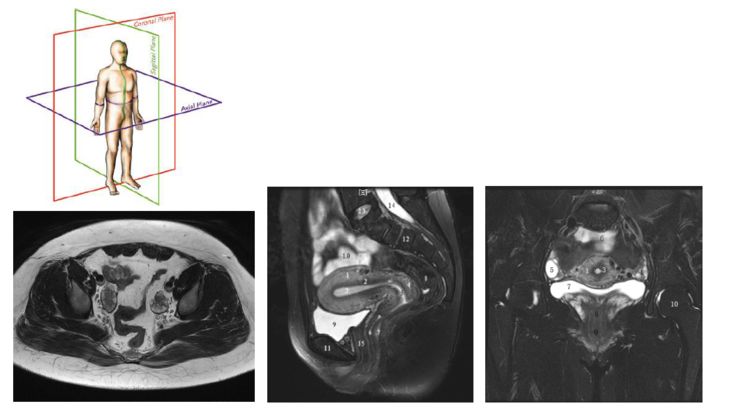

通常,我们在临床上采集的经典图像方位是横轴位,矢状位和冠状位。最常用的是横轴位图像。

上图就是一个横轴位图像,我们能看到骨头,能看到双侧卵巢,能看见卵泡,它是最常用的。中间的这个图像是矢状位,和之前看的解剖图一样,能看见子宫内膜、结合带、肌层和浆膜、宫颈,这张图是女性盆腔里大家最愿意看到的一张图。它最直观,如果患者长了肌瘤和畸形,都可以看得特别清楚。后面这个是冠状位,主要作为参考,这个图像上能看到卵巢相对位置等等一般观察女性盆腔,主要使用的是横轴位图像和矢状位图像。